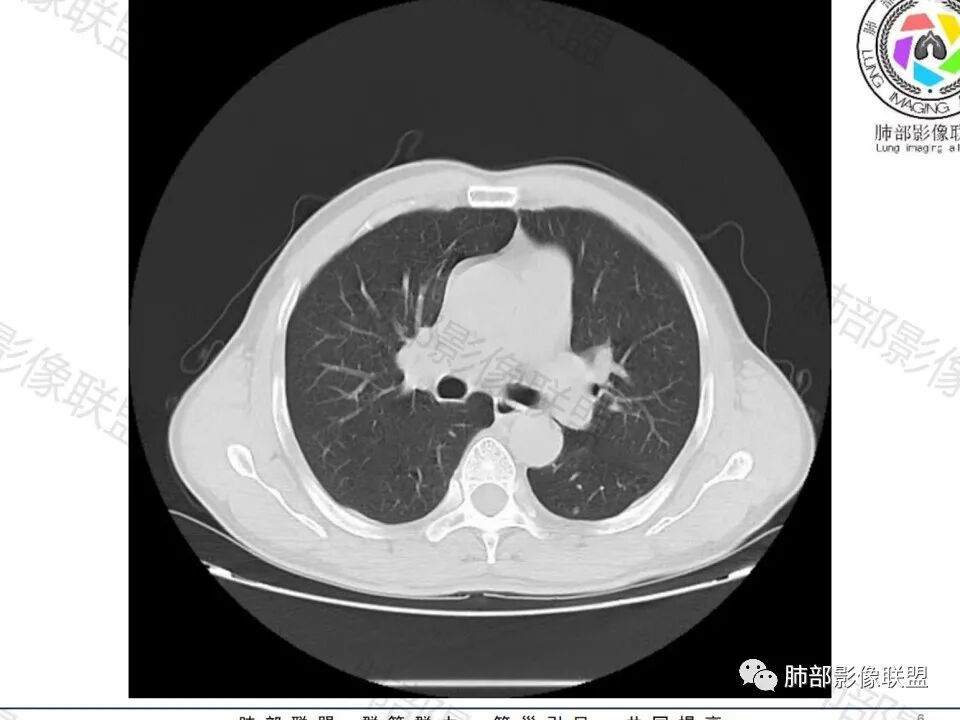

老年男性,无症状,肺气肿背景

类圆形,边缘稍平直,周围晕中细微毛刺,密度均匀,均匀强化,血管走形自然,稍牵拉扭曲,支气管在近端堵塞

多发类似结节

大家目前碰到多数结节是磨玻璃结节,对于实性结节的诊断反而陌生,其实性结节才是考验脑子的时候;

这枚结节的纵隔窗在没有调节窗位的情况下,已经很密实了,说明这个结节里面是软组织的成分,这与普通炎性结节(隐球菌等)的密度还是有区别的,很多年前就有人提出,纵隔窗显示越大,恶性可能越大;

结节周围有磨玻璃影,边界似清不清的,但是总体不如炎性晕征那么模糊;